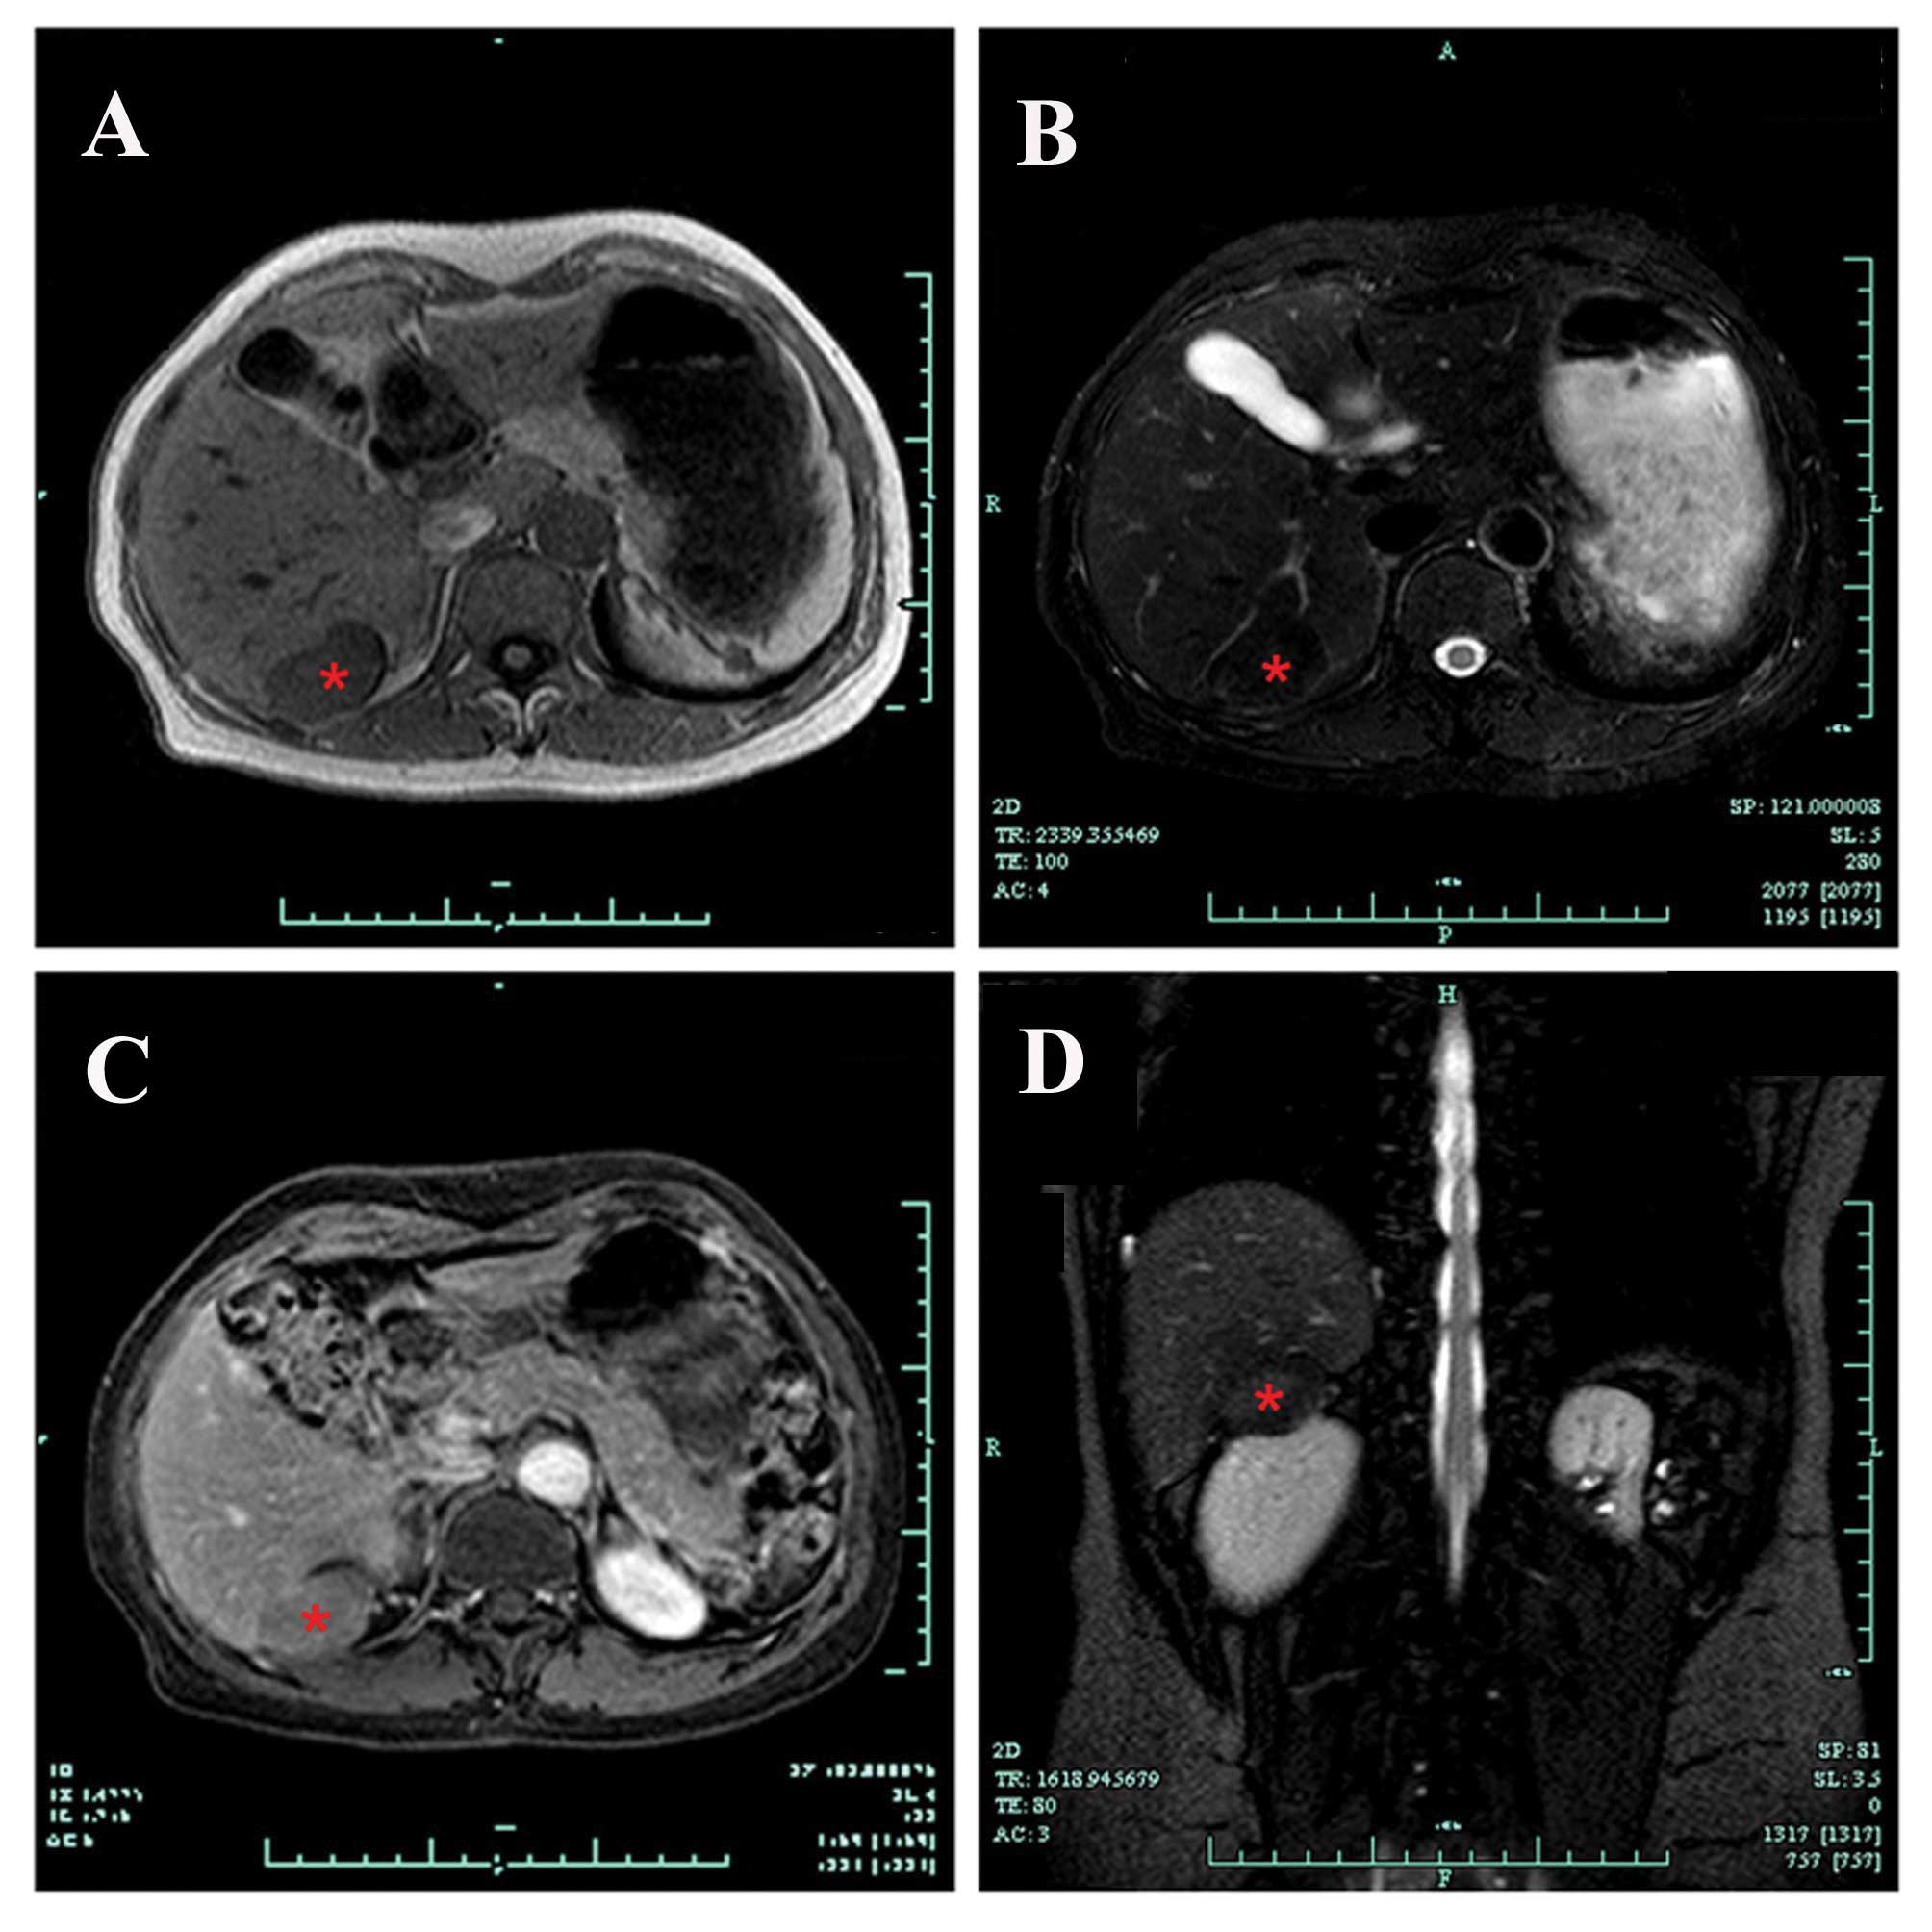

Rare presentation of a right retroperitoneal accessory spleen: A case report

An accessory spleen is a congenital malformation, which is defined as ectopic splenic parenchyma. Here, an extremely rare case of a right retroperitoneal accessory spleen, mimicking a retroperitoneal neoplasm, is reported. A 40-year-old woman was referred following the incidental detection of a retroperitoneal neoplasm. Computed tomography and magnetic resonance imaging scans confirmed the presence of a retroperitoneal neoplasm at the hepatorenal recess. Retroperitoneoscopic excision was conducted, with excellent results. Pathological examination of the resected specimen revealed splenic tissue. In conjunction with a review of the literature and a discussion of the salient radiological features, the present case highlights the requirement for accurate preoperative diagnosis of an accessory spleen in the right retroperitoneal space, in order to avoid unnecessary surgical intervention.